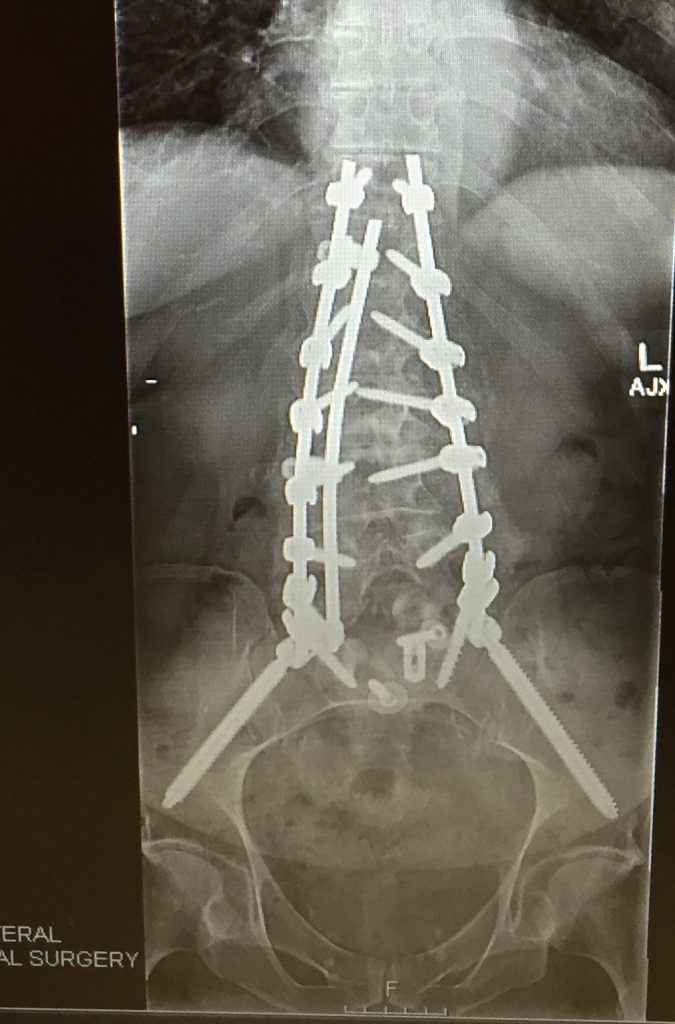

Dr. Huang fused from T11 through my sacrum, adding stabilizing bolts from the sacrum to my pelvis. I have three 14-inch rods, close to twenty screws, and a “cage” set in between L5 and S1. The instrumentation reveals itself in x-ray as a "construction project." I believe this is commonly called a TLIF.